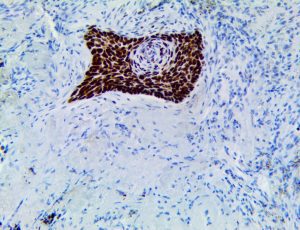

It is the ICU physician who is most likely to witness one of the deadliest manifestations of the abnormal immunological response, the cytokine storm syndrome (CSS). This response is also referred to by some as the cytokine release syndrome (CRS). CSS is characterized by continuous activation and expansion of macrophage and lymphocyte populations, which secrete large amounts of cytokines, causing the cytokine storm. This massive cytokine release is akin to hemophagocytic lymphohistiocytosis (HLH) disease, a syndrome characterized by initial unchecked and persistent activation of cytotoxic T lymphocytes and NK cells.

Clinical and laboratory manifestations of HLH include fever, enlarged liver and/or spleen, neurologic dysfunction, coagulopathy, liver dysfunction, cytopenias (i.e., low levels of erythrocytes, leukocytes, and/or platelets), hypertriglyceridemia, hyperferritinemia, hemophagocytosis, and eventually diminished NK cell activity as the immune system becomes progressively paralyzed. HLH can be familial (primary HLH) or secondary to another disease process (sHLH), such as rheumatic disease, in which it is referred to as macrophage activation syndrome (MAS, characterized by elevated ferritin).